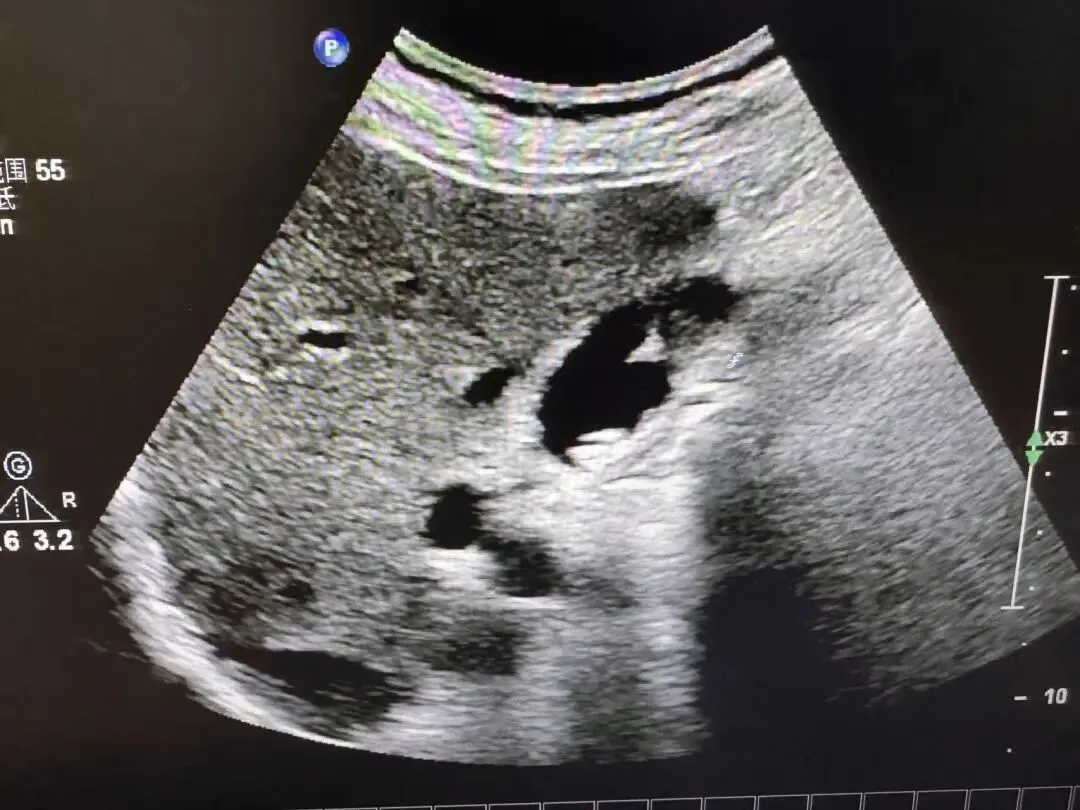

胆囊壁增厚,胆囊内透声差,其内稀疏或密集的细小或粗大光点

胆囊肿大,胆囊壁增厚,胆囊内透声差,充满稀疏或密集的细小或粗大光点

囊壁增厚,呈“双边影”